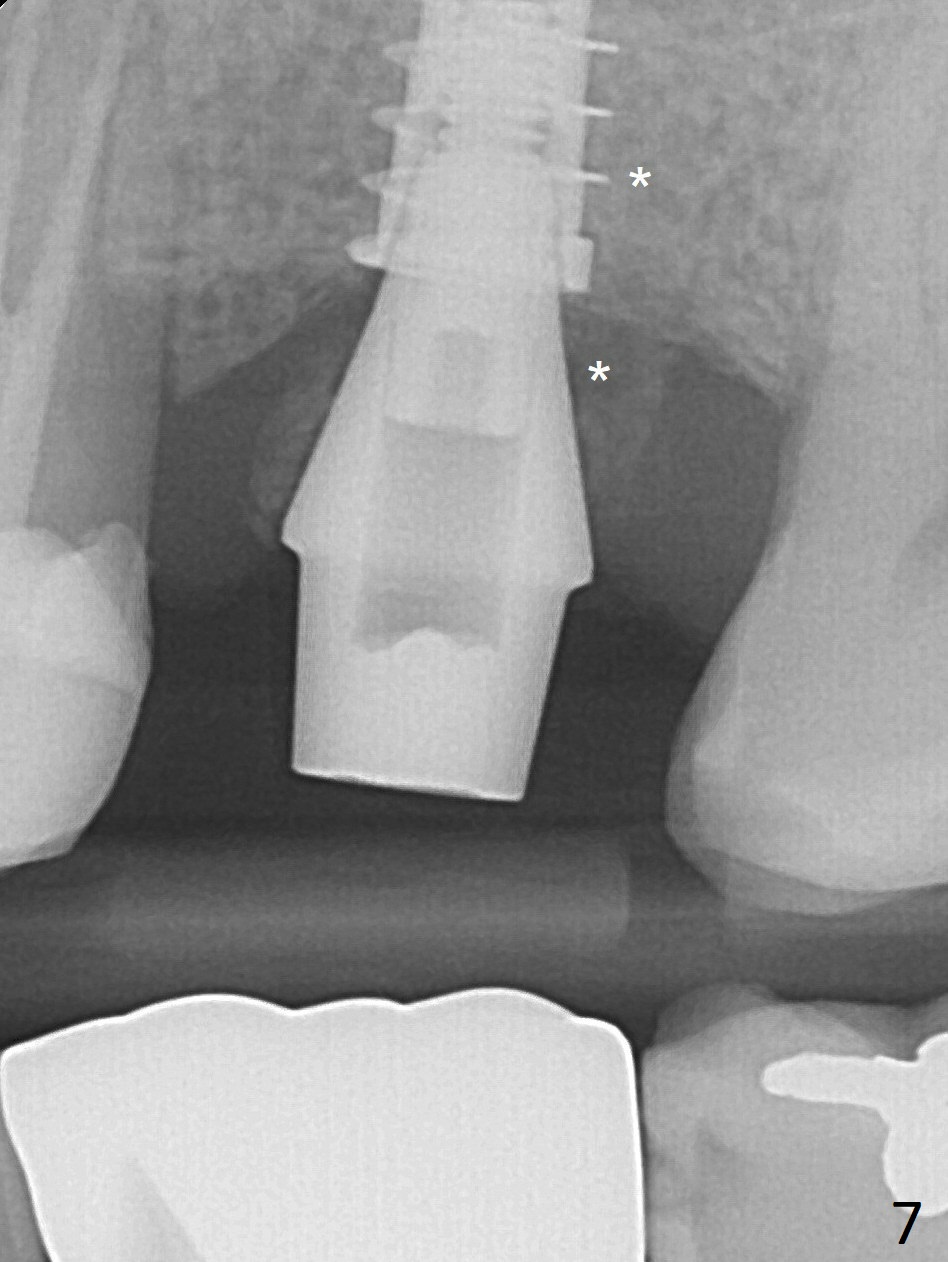

Osteogen plug and allograft (Fig.7 *) are inserted into the remaining distobuccal socket (reduced after bone expansion).  The distal socket appears to heal while the bone graft remains at the crest 5 months postop (Fig.11).